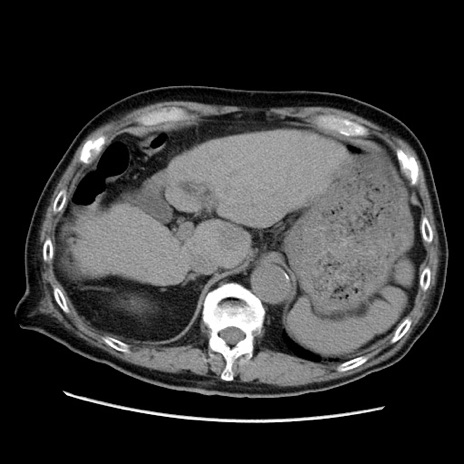

冠状断像

【症例】70歳代男性

【主訴】腹痛

【現病歴】肝硬変・肝細胞癌にてかかりつけの方。約9時間前に食後より腹痛出現。症状が徐々に増悪し、嘔吐出現したため来院。

【既往歴】肝硬変、肝細胞癌(RFA、TACE後)

【身体所見】意識清明、表情苦悶様、BT 36℃、BP 129/78mmHg、P 88bpm、SpO2 97%(RA)、右上腹部から心窩部にかけて圧痛あり、反跳痛なし、筋性防御あり。

【データ】WBC 5800、CRP 0.16